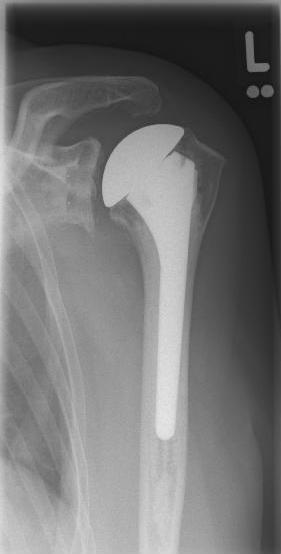

left: X-ray image of a short-shaft prosthesis

right: Short-shaft prosthesis (Affinis Short type, Mathys company)